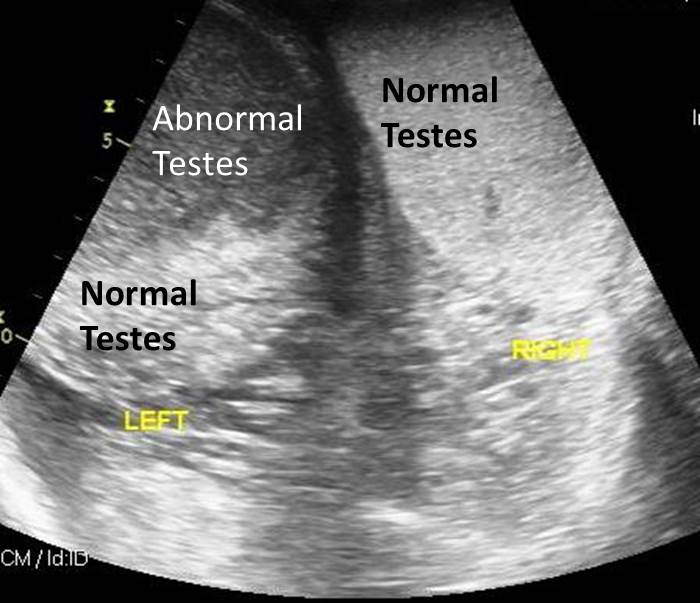

Figure 1 from Testicular Torsion with Ureteral Entrapment in a Dog

[PDF] Testicular Torsion with Ureteral Entrapment in a Dog Archives on Testicular Torsion In Dogs ultrasonographic findings of testicular torsion in dogs comprise testicular enlargement with decreased echogenicity,. testicular torsion is defined as a twisting of the testis or testicle on its connective tissue. overview of canine testicular torsion. the purpose of this review is to provide a comprehensive comparison of spermatic cord torsion in domestic animals. testicular swelling in. Testicular Torsion In Dogs.